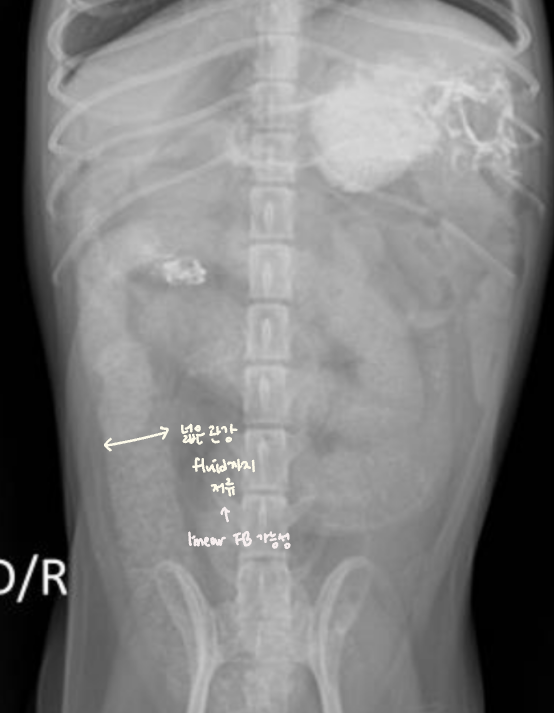

Fluid or Mass

- Fluid : ์ธ์ธก์์์ ์ค์์ผ๋ก ๋ชจ์. diffuseํ ์ฐ๋ถ์กฐ์ง ๋ฐ๋.

- Mass : ์๋ฆฌ๋ฅผ ์ฐจ์งํจ โ ์ฅ์ ๋ฐ์ด๋. & ์ข ์์ด ์ปค์ง๋ฉด์ ์ถํ์ ์ ๋ฐ.